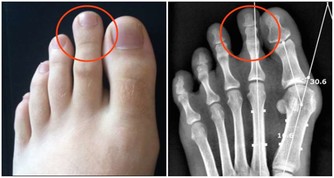

1.公孫穴(在腳內側,也就是大腳趾關節後邊有一個突出的骨頭,就在這個骨頭後的凹陷處)